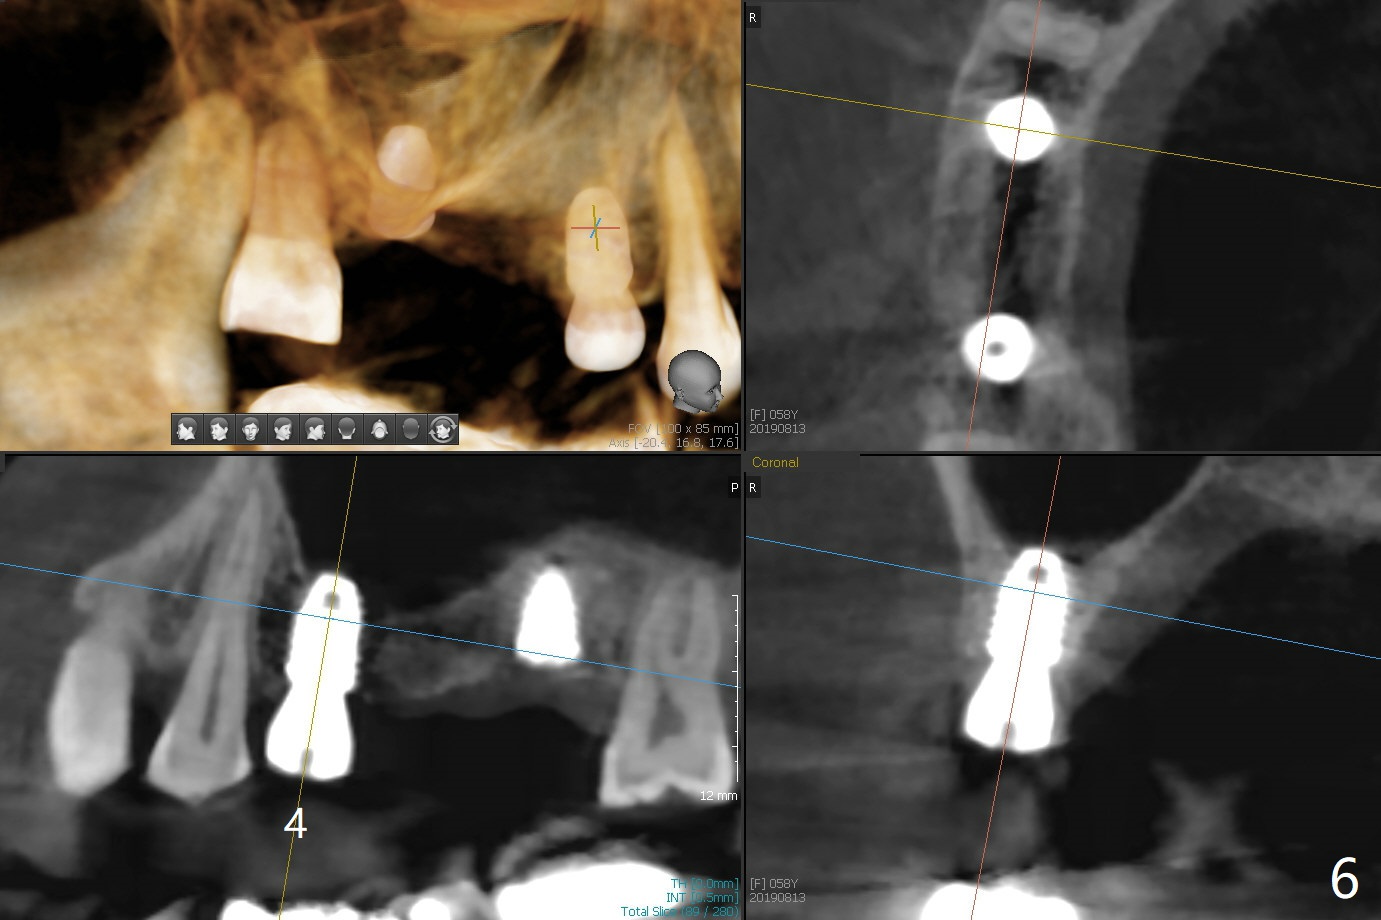

Eight months post socket preservation, the bone density at #2 feels low during osteotomy.  The site is underprep not only in depth, but also in diameter (4.0x7.3 mm with 10.5 mm offset), but a 5x7.3 mm implant is ~ 1 mm shy of the purposed depth.  Following 4.5x7.3 and 4.0x8.5 mm drills (without air leak), the implant reaches the depth, but with ~ 5 Ncm insertion torque (Fig.1).  Placement of the same sized implant at #4 (healed site) is smooth with satisfactory stability (~30 Ncm, Fig.2,3).  Ideally the site of #2 should have been prepared with sinus lift so that the apex of a longer implant would be engaged to the sinus floor for stability.  These two implants heal normally clinically and radiographically 1.5 months postop (Fig.4-6).  Bone surrounds the implant at #2 when it is uncovered 4 months postop (Fig.7).  The retainer at #4 looks short with large gingival embrasure (Fig.8 *) 6.5 months postop.  Finally the patient is ok with it because she does not like gingivectomy.  Provisional should have fabricated (Fig.9 light yellow curved lines) to create gingival scallops with secondary formation of papillae (arrows).